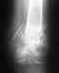

Перелом двух лодыжек и таранной кости без смещения

6.04.2013года меня сбила машина, сразу же доставили в больницу, сделали рентген - перелом двух лодыжек без смещения, плюс перелом таранной кости без смещения.... Вставили спицы - зафиксировали сустав (без гипса), две недели пролежал в больнице, сейчас уже дома. Врач сказал приходить через три недели...(доставать спицы), то есть это в общей сложности получается 5 недель со спицами...Сейчас нога не болит, опухлость почти спала, пальцами шевелю без проблем... Хотелось бы узнать ваши прогнозы по данному случаю.., восстановится ли подвижность сустава и как скоро я встану на ноги...? И какие могут быть последствия перелома в дальнейшем...? Заранее благодарен

• Кликните для загрузки файла DSC_1895.JPG